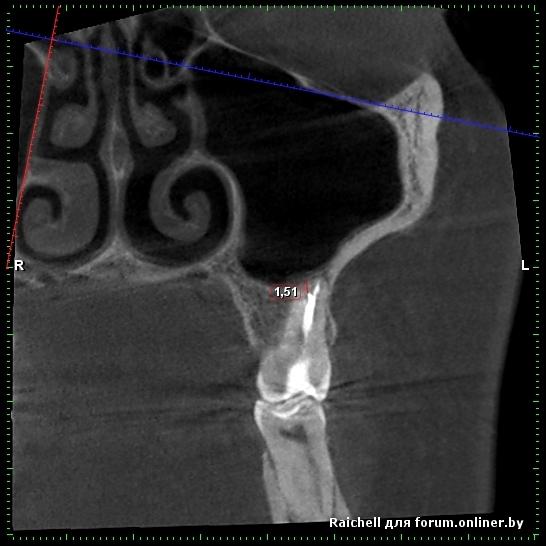

Во всех депульпированых зубах есть проблемы, плюс в пазухе слева от 25 зуба есть нюанс

inycik:Во всех депульпированых зубах есть проблемы, плюс в пазухе слева от 25 зуба есть нюанс

16,15 на удаление, потом синус и имплантация

Все зубы перелечила. это кт до лечения. Сейчас под временными коронками. Предлагают имплантацию 1.5,2.5 и 4.5 (убрать мост, т.к. 4.6 сильно разрушен). 1.5 удалить и сразу же имплант, но про наращивание не говорили.

А скажите, что в пазухе? Это как-то повлияет на имплантацию